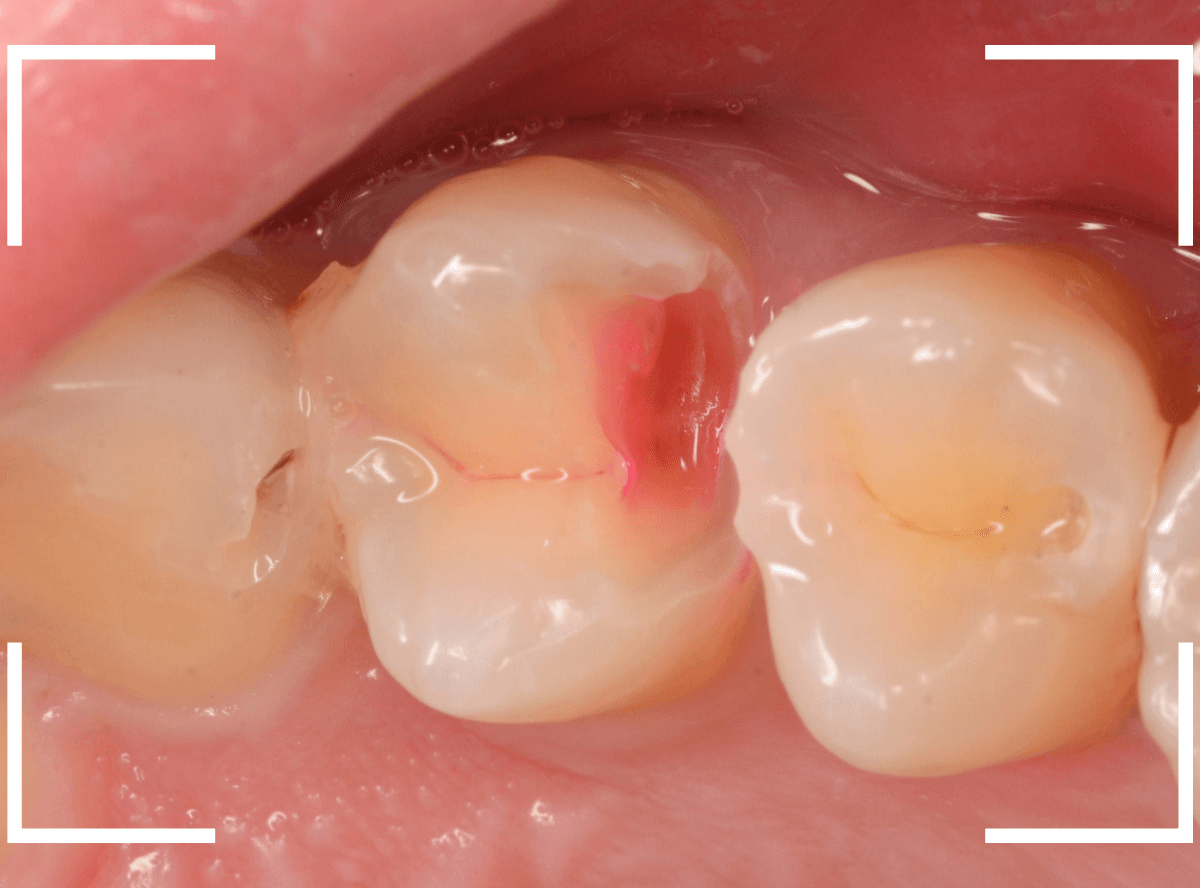

Case.23 歯のすきまから両側が大きな虫歯

「下の奥歯が痛む」という訴えで来院された患者さんのケースです。

目視でも、手前の奥歯がかけていて、中で虫歯が広がってるであろうことは予想できます。

ピンセットで歯を叩いてみても、手前の奥歯が痛むようです。

レントゲン写真で確認します。

青い線が神経、赤い線が虫歯の範囲です。

奥歯の方がより深い虫歯に見えますが、再度打診で確認したところ、やはり手前の奥歯が痛むそうです。

状況から、まず手前の奥歯から治療となりました。

麻酔をして、手前の奥歯のレジンを慎重に外します。

前に虫歯の治療をした時点で、神経スレスレの状態でしたので、削りすぎないように慎重にレジンを外さなければいけません。

レジンを外して、う蝕検知液で確認します。

レジンの中で虫歯が進行していたのがわかります。

慎重に全ての虫歯を除去しました。

何とか、神経が露出せずに済んでいます。

お薬をつめて、セメントで蓋をして経過観察します。

後日、状況を確認したところ、虫歯処置した後も、手前の奥歯が痛むとの事でした。

「我慢できないほどでもない」との事でしたので、引き続き経過観察しつつ、奥歯の治療を治療する事になりました。

奥歯は、レントゲンで見た通り、少し歯を削るとすぐに虫歯の穴が出てきました。

こちらは、ある程度虫歯を取ったところで染め出してみると真っ赤です。

ですが、何とか神経に達する前に、全ての虫歯を除去できました。

神経の治療が必要かと思っていたので、その点は幸運でした。

奥歯もお薬をつめて、セメントで蓋をして経過観察です。

何とか神経を取らずに済ませたいですが、どうなる事か・・・。